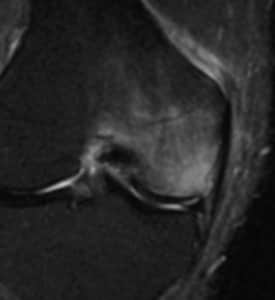

ちなみに内側(小指側)が痛いものは「上腕骨内上顆炎」といいます。 膝が痛い 膝の痛みには、事故やスポーツ外傷などで急に発生するもの、運動のやりすぎによるもの、中年以降慢性的に起きてくるものがあります。 外傷による障害の代表的なものとして半月板損傷、靱帯の損傷があげられます。上記の画像は膝の骨挫傷(こつざしょう)を MRI撮影したものです。 こちらのサイトを参考にしてみてください。 ↓↓↓ Medical Note「MRI画像あり骨挫傷とは?症状や診断、治療まとめ!」 転倒や捻挫などの原因がない関節の痛みは要注意! 今回、私の右足首の骨挫傷(こつざしょう)は日本大百科全書(ニッポニカ) 骨挫傷の用語解説 骨折しているのではなく、骨の内部が損傷している状態をいい、出血や炎症および強い痛みを伴う。打撲や転倒などの衝突によって外部から鈍的な圧力が加わった場合におこり、手指の中手骨や膝(しつ)関節および足関節の外傷などの際によくみられ

12 骨挫傷および半月板損傷 特定医療法人 同心会 遠山病院